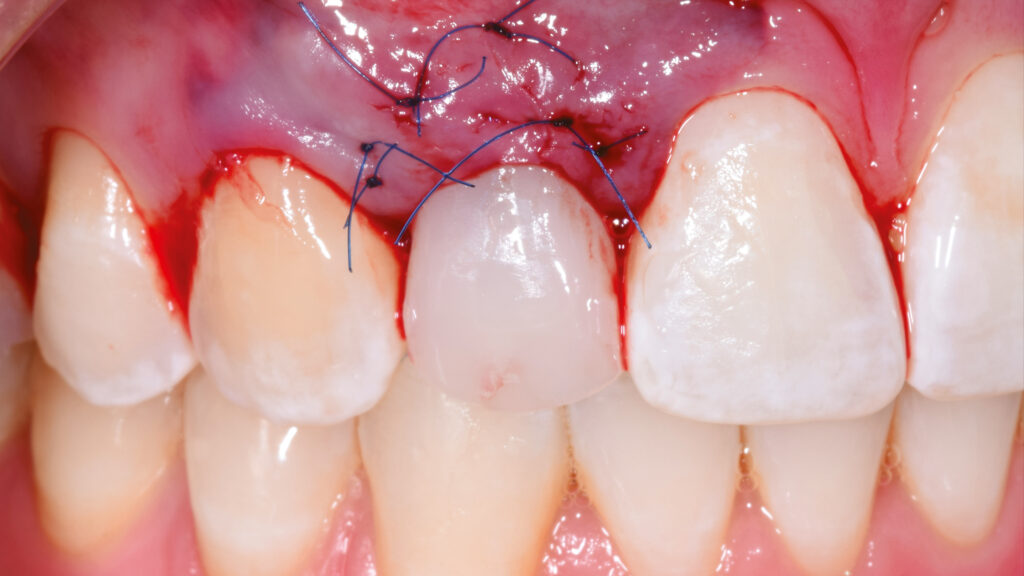

Paradigmenwechsel:

Virtuelle Implantologie

In der Zahnarztpraxis wird der Milchzahn schonend extrahiert und das TempShell-Provisorium mit seinen zwei Flügeln im Mund des Patienten einprobiert (Abb. 38). Nach der Sofortimplantation des Implantates regio 12 erfolgt eine Konturverbesserung, die im Rahmen der Freilegung korrigierend zur Weichgewebsverdickung vorgenommen wird. Dadurch soll ein graues Durchschimmern des Titans verhindert werden (Abb. 39). Einige Wochen später kommt der Patient zur Kontrolle in die Praxis. Die Heilung der Gingiva ist gut. Das Gingivaniveau konnte weiter nach apikal gelegt werden, um einen harmonischeren Gingivaverlauf zu erzielen (Abb. 40 und 41).

Nach der Heilung des Weichgewebes sind die arkadenförmige Kontur der Gingiva und die Papillen deutlich zu erkennen (Abb. 42 und 43). Etwa sechs Monate nach der Osseointegration und Konditionierung der Gingiva wird die Situation mit dem Intraoralscanner erfasst, um mit der Herstellung der implantatprothetischen Versorgung fortzufahren. Nach dem Aufschrauben des Scanbodys auf das Implantat erfolgt der Scanvorgang (Abb. 44). Intraoralscanner gehören zu den aufregendsten neuen Technologien in der Zahnmedizin. Die digitale Abformung bietet dem Patienten deutlich mehr Komfort. Zudem werden klinische Abläufe vereinfacht und die Kommunikation mit dem Zahntechniker verbessert. Im nächsten Schritt werden die STL-Dateien für den Modelldruck aufbereitet (Abb. 45). Vor dem Scannen der gedruckten Modelle muss das Modellanalog regio 12 eingesetzt werden. Das Modell mit abnehmbarer Gingivamaske ist für die Aufnahme des Modellanalogs durch eine Öffnung vorbereitet und besitzt im unteren Bereich des Ausschnittes eine Art Verriegelungsmechanismus (Abb. 46). Dies gewährleistet einen sicheren Presspassung und eine korrekte, automatisch zentrierte Einschubposition (Abb. 47).

Eingliederung der Implantatkrone

Nach einigen Monaten war das periimplantäre Weichgewebe endgültig stabilisiert. Es zeigte sich noch eine leichte Narbenbildung am Gingivazenit. Nach vorsichtigem Ausdrehen der provisorischen TempShell-Krone offenbart sich eine gut ausgebildete Weichgewebsarchitektur. Die Gewebedicke an der Implantationsstelle ist vergleichbar mit der Situation am zu kopierenden linken lateralen Schneidezahn (Abb. 64). Die Zirkonoxidkrone mit Titanadapter wird definitiv mit dem Implantat verschraubt. Durch die detaillierte digitale Vorbereitung sind oft nur kleine Korrekturen notwendig. Meist können die Restaurationen ohne Einprobe eingegliedert werden. Die biokompatiblen Anteile der Implantatkrone (Titanadapter) und die subgingivalen Anteile der Implantatkrone gewährleisten eine optimale Anlagerung der Gingiva (Abb. 65). Der spaltfreie Sitz der Versorgung auf dem Implantat wird röntgenologisch kontrolliert.

Abschließend kann der Schraubenkanal mit Teflonband und Komposit verschlossen und die statische und dynamische Okklusion überprüft werden. Bei der Eingliederung einer Frontzahnimplantatkrone kommt es vor allem auf eine ästhetische Integration an. Neben der weißen Ästhetik ist die rote Ästhetik mit der Ausformung des Emergenzprofils und der Harmonie des Gingivaverlaufs wichtig. Die Restauration fügt sich ästhetisch gut in die Zahnreihe ein (Abb. 66 bis 68). Das Zusammenspiel der dentalen und gingivalen Umgebung sowie der Lippen mit der prothetischen Versorgung ergibt ein harmonisches Gesamtbild (Abb. 69). Einige Monate nach dem Einsetzen der Implantatkrone hat sich die Gingiva sichtbar gut erholt (Abb. 70).